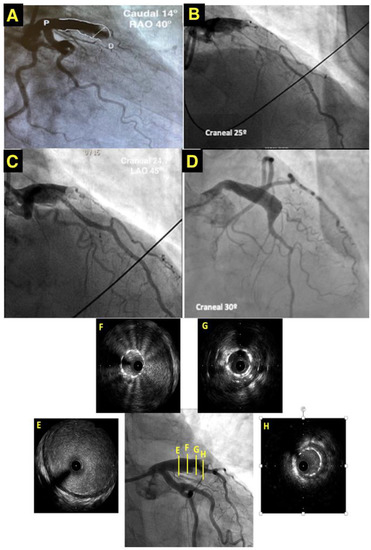

Coronary artery aneurysm (CAA) presenting as an ST-elevation myocardial infarction (STEMI) represents a clinical challenge due to the technical difficulties in the percutaneous management of this specific situation. Appropriate treatment for CAA depends on the precise clinical situation and consists of medical management, [...] Read more.

Coronary artery aneurysm (CAA) presenting as an ST-elevation myocardial infarction (STEMI) represents a clinical challenge due to the technical difficulties in the percutaneous management of this specific situation. Appropriate treatment for CAA depends on the precise clinical situation and consists of medical management, surgical resection, or/and stent placement. The high rate of complications during percutaneous intervention (distal thrombus embolization, no-reflow phenomenon, stent malposition, or dissection) makes emergent surgery a frequent situation in these cases. We present the case of a 50-year-old man with a STEMI due to thrombotic occlusion of CAA. Specific angiographic techniques and intracoronary imaging help with the percutaneous management of acute thrombotic occlusions in CAA, providing a less invasive approach than emergent surgery. Full article

Show Figures

Figure 1